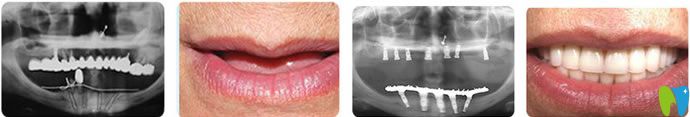

這個(gè)春節(jié)怎么過(guò),吃喝玩樂(lè)溜一遍。較近不少人咨詢(xún)小開(kāi)深圳種植牙哪家好,都是想讓父母在春節(jié)前有一口好的牙齒,吃嘛嘛香。小編整理了一份鵬程口腔種植技術(shù)及價(jià)格,供大家參考哦!